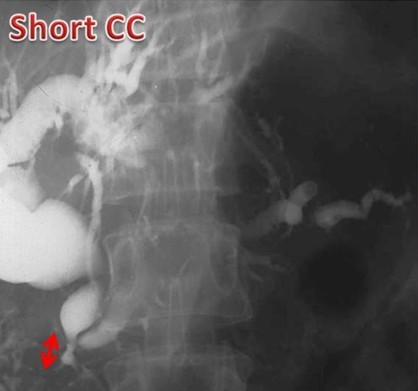

The reporting of the ERCPs was done in a stepwise fashion. The first step was to identify ERCPs in which both ducts were filled and pancreaticobiliary confluence was clearly identified in more than one image (inclusion criteria for study) (Figure 1). ERCPs in which only one duct (pancreatic or biliary) was filled or the confluence of the pancreatic and bile ducts was not clearly visualized were excluded from the study (Figure 1). Second, in those ERCPs included in the study, we then reported on whether the pancreatic and bile ducts opened into the duodenum separately or if the ducts were joined to each other and a common channel opened into the duodenum(Figure 2). Third, we measured the length of the common channel in the latter (Figure 3). To do so, we measured the actual length of the channel as it appeared on the images and corrected it with a magnification factor, as determined by the actual and imagined (as on images) width of the endoscope [15, 21]. If the corrected length of the united duct was less than 6 mm, it was reported as a short common channel. If the corrected length of the united duct was between 6 and 15 mm, it was reported as a long common channel. If the corrected length of the common channel was more than 15 mm, it was presumed that the ductal union had occurred outside the duodenal wall and such patients were reported as having anomalous pancreaticobiliary ductal union [20, 22]. For patients with anomalous pancreaticobiliary ductal union, we determined the pattern and angle of the ductal union. Anomalous pancreaticobiliary ductal union was reported as P-B type when the pancreatic duct appeared to join the bile duct and B-P type when the bile duct appeared to join the pancreatic duct. The angle of union was the actual angle at which the union occurred between two ducts [23].

Figure 3. Three ERCP images showing the definition of a short common channel (short CC: channel length 3 mm), a long common channel (long CC: channel length 12 mm) and anomalous pancreaticobiliary ductal union (anomalous pancreaticobiliary ductal union: channel length 4 cm). CC: common channel; PBDU: pancreaticobiliary ductal union |